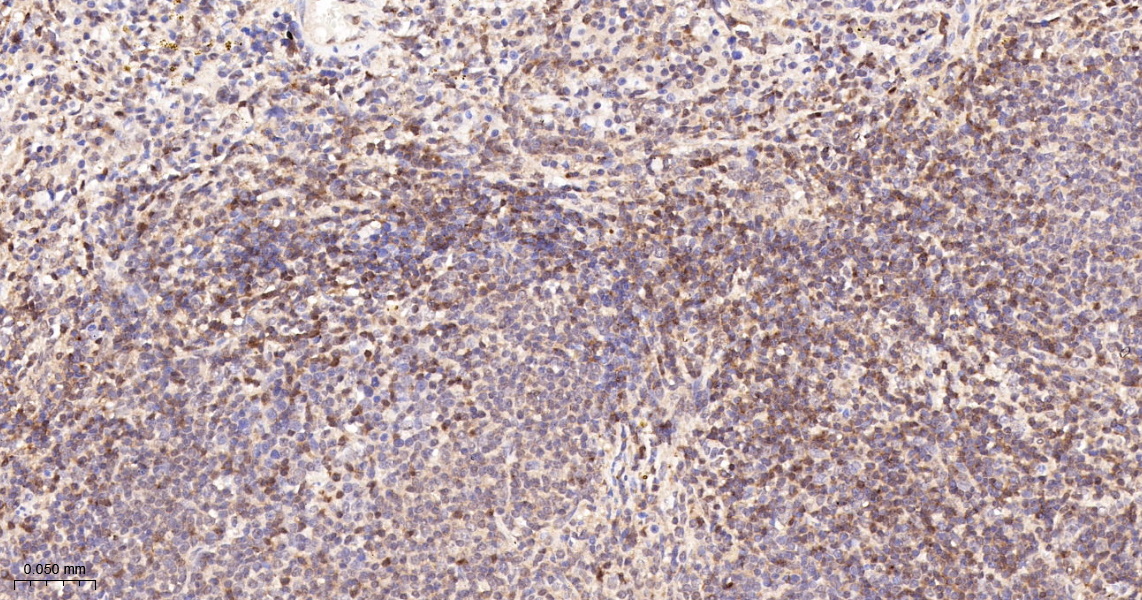

IHC-P 1:200-400